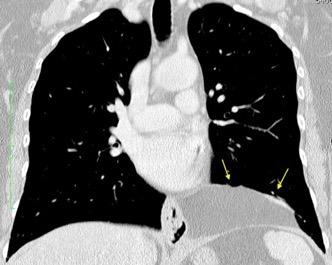

37. ESPLENOSIS TORÁCICA

Autotrasplante de tejido esplénico al tórax tras trauma. (T. Penetrante más frecuente que cerrado)

Causas:

1. Trauma 2.Esplenectomía

3. Diseminación hematógena

4. ¿Hipoxia?

T1: Hipointenso

T2: Hiperintenso. Puede ser hipointenso. (Hierro)

Esplenectomía previa

Ferrer TM et al. Thoracic splenosis: History is the key. Respiratory Medicine Case Reports. 2017